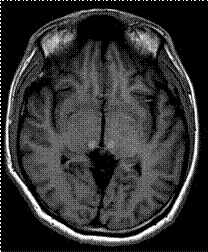

Las mujeres heterocigotas también pueden desarrollar síntomas de deterioro neurológico, siendo los más reportados el deterioro cognitivo, vértigo, ataxia, hemiparesia, síntomas sensitivos hemicorporales y cefalea. En la mitad de las pacientes, la presentación clínica fue compatible con afectación dentro del territorio vertebrobasilar, mientras que el territorio carotideo estaba definitivamente comprometido en sólo el 10% de los casos.25 También se han informado oclusiones de la arteria central de la retina 28 y oclusiones de la vena central de la retina.29 Además de la dolicoectasia, en los estudios de imagen se pueden observar lesiones de sustancia blanca y el “signo del pulvinar” caracterizado por hiperintensidad en la región posterior de tálamo, en la secuencia T1 de la resonancia magnética.9